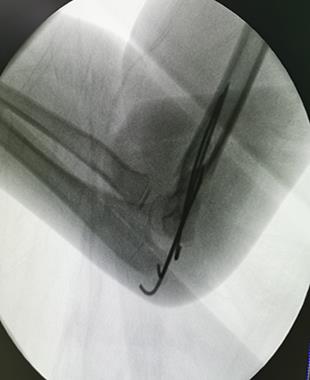

儿童前臂双骨折闭合复位弹性髓内针内固定术

儿童前臂双骨折闭合复位弹性髓内针内固定术(术后伤口外观仅缝合1针)